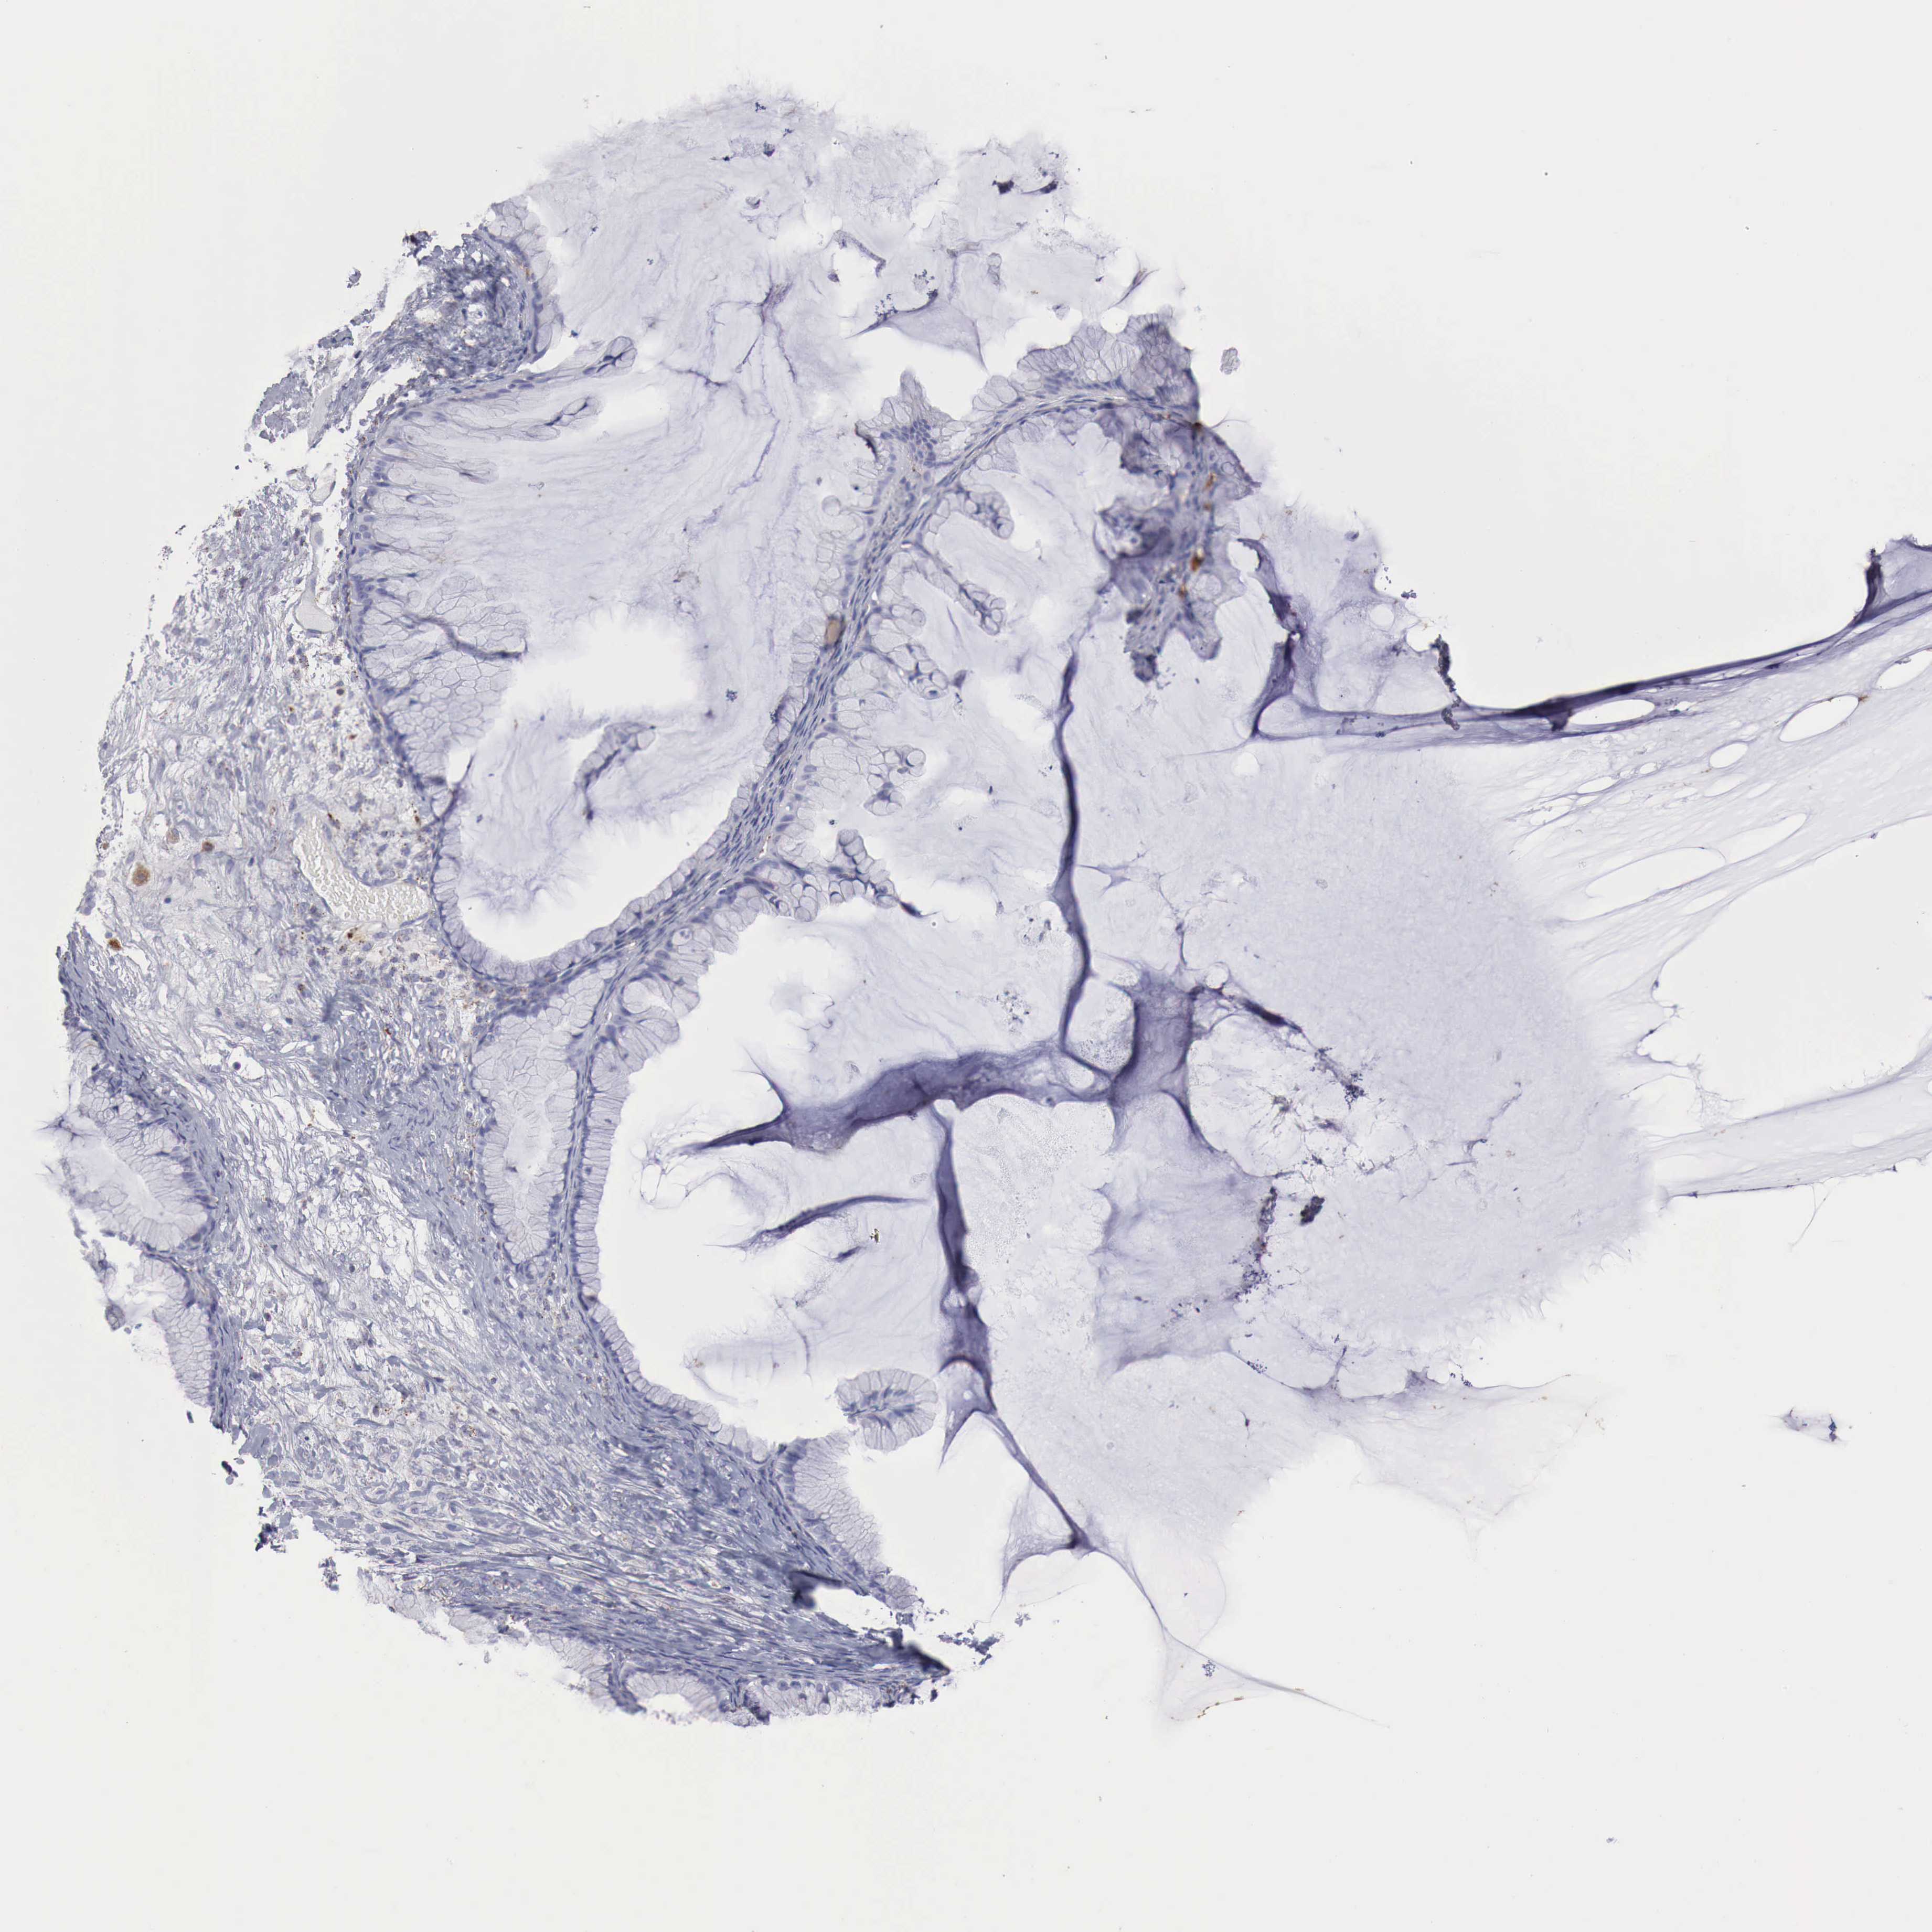

OVARIAN CANCER - Protein expressioni

A mouse-over function shows sample information and annotation data. Click on an image to view it in a full screen mode. Samples can be filtered based on level of antibody staining by selecting one or several of the following categories: high, medium, low and not detected. The assay and annotation is described here.

Note that samples used for immunohistochemistry by the Human Protein Atlas do not correspond to samples in the TCGA dataset.

Antibody stainingi

Antibody staining in the annotated cell types in the current human tissue is reported as not detected, low, medium, or high, based on conventional immunohistochemistry profiling in selected tissues. This score is based on the combination of the staining intensity and fraction of stained cells.

Each image is clickable and will lead to virtual microscopy that enables deeper exploration of all samples and also displays staining intensity scores, fraction scores and subcellular localization as well as patient and tissue information for each sample.

Antibody HPA000237

Antibody HPA000966

Cystadenocarcinoma, mucinous, NOS

Carcinoma, endometroid

Cystadenocarcinoma, serous, NOS